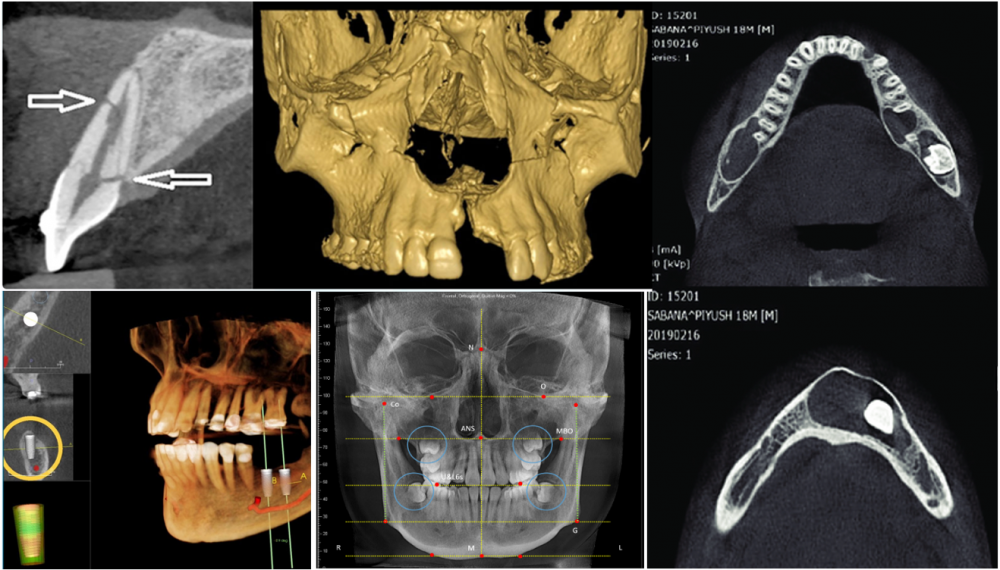

CT Cone Beam (Cone Beam Computed Tomography – CBCT) là hệ thống chẩn đoán hình ảnh nha khoa tích hợp, cho phép thực hiện chụp X-quang pano, ceph và CT 3D trên cùng một thiết bị. Tùy theo chỉ định lâm sàng, bác sĩ có thể lựa chọn chế độ chụp phù hợp để đánh giá tổng quan hoặc phân tích chuyên sâu cấu trúc hàm – mặt.

Ở chế độ CT 3D, máy CBCT sử dụng tia X dạng hình nón quét quanh vùng hàm – mặt để thu nhận dữ liệu không gian, sau đó tái tạo thành hình ảnh ba chiều trên phần mềm. Nhờ đó, bác sĩ có thể quan sát rõ xương hàm, chân răng, xoang hàm và vị trí dây thần kinh với độ chính xác cao hơn so với phim 2D.

X-quang pano và ceph là các kỹ thuật chụp hai chiều, thường được dùng để khảo sát tổng quan răng, khớp cắn và cấu trúc xương hàm. Trong khi đó, CBCT ở chế độ 3D cung cấp hình ảnh không gian, cho phép đo đạc chiều cao, chiều rộng và mật độ xương cũng như mối liên quan giữa răng và các cấu trúc giải phẫu quan trọng.

Ở chế độ CT 3D, CBCT cho phép tái tạo hình ảnh không gian của mô cứng vùng hàm – mặt, bao gồm xương hàm, chân răng, xoang hàm và ống thần kinh. Nhờ khả năng xem theo nhiều lát cắt và nhiều góc độ, bác sĩ có thể đo chính xác chiều cao, chiều rộng và hình dạng xương – những thông tin mà phim X-quang 2D khó thể hiện đầy đủ.

- Chuyển đổi dữ liệu DICOM thành mô hình 3D: Ảnh CBCT sau khi chụp được xuất ở định dạng DICOM và xử lý bằng phần mềm chuyên dụng để dựng ảnh 3D, lát cắt và bản đồ mật độ xương.

- Phân tích và mô phỏng điều trị: Phần mềm cho phép đo chính xác khoảng cách tới dây thần kinh, mật độ xương (grey value approximation), và mô phỏng vị trí đặt trụ implant. Tính năng mô phỏng giúp bác sĩ thử các kịch bản đặt implant khác nhau để chọn phương án an toàn nhất.